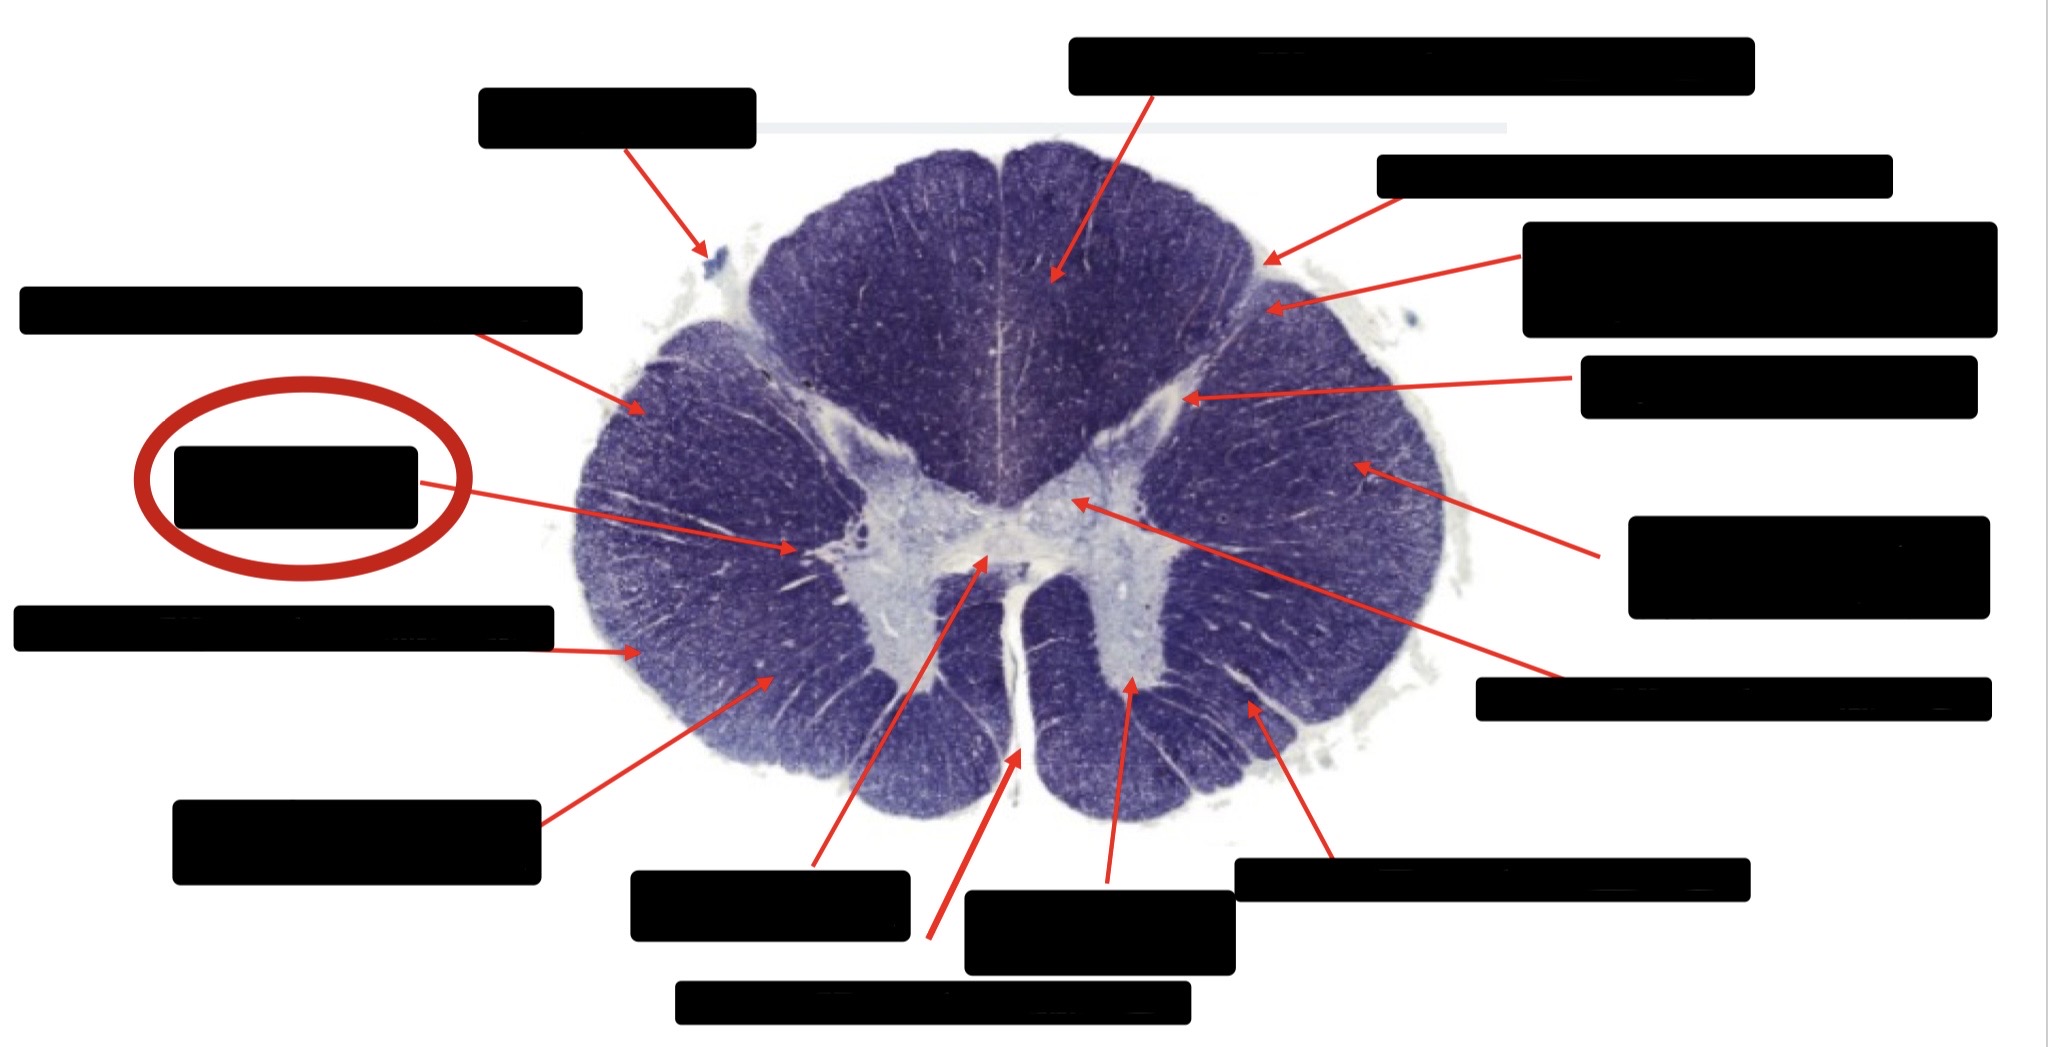

Posterior Column

Large Fiber Entry Zone

Posterior Spinocerebellar Tract

Clarke’s Nucleus

Anterior Spinocerebellar Tract

Ventral Root Fibers

Central Canal

Lissauer’s Tract & Small Fiber Entry Zone

Substantia Gelatinosa

Lateral Corticospinal Tract

Spinothalamic Tract

Anterior Horn Motor Neurons (Distal Muscles)

Anterior Horn Motor Neurons (Proximal Muscles)

Dorsal Rootlet

Lateral Horn